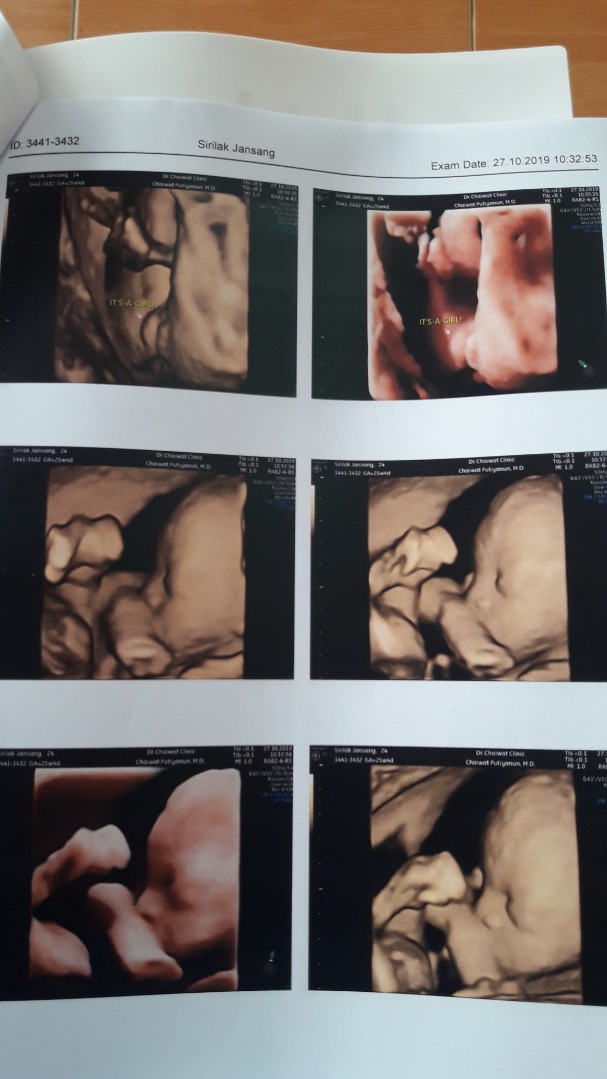

💕

22w

ซาว22wชัดมากค่ะ